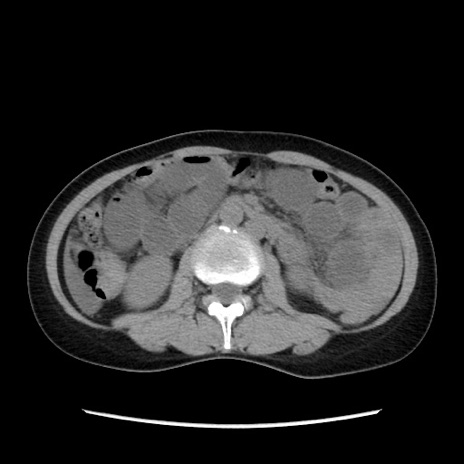

症例32(横断像)

【症例】40歳代 女性

【主訴】上腹部痛、嘔気・嘔吐

【現病歴】約9時間前頃から急に上腹部痛、嘔気、嘔吐が出現。改善しないため救急要請。

【既往歴】子宮頚癌(広汎子宮全摘術、放射線療法)、腸閉塞

【身体所見】腹部:平坦、軟、腸雑音亢進、上腹部を中心に腹部全体に圧痛あり。

【データ】WBC 8400、CRP 0.03